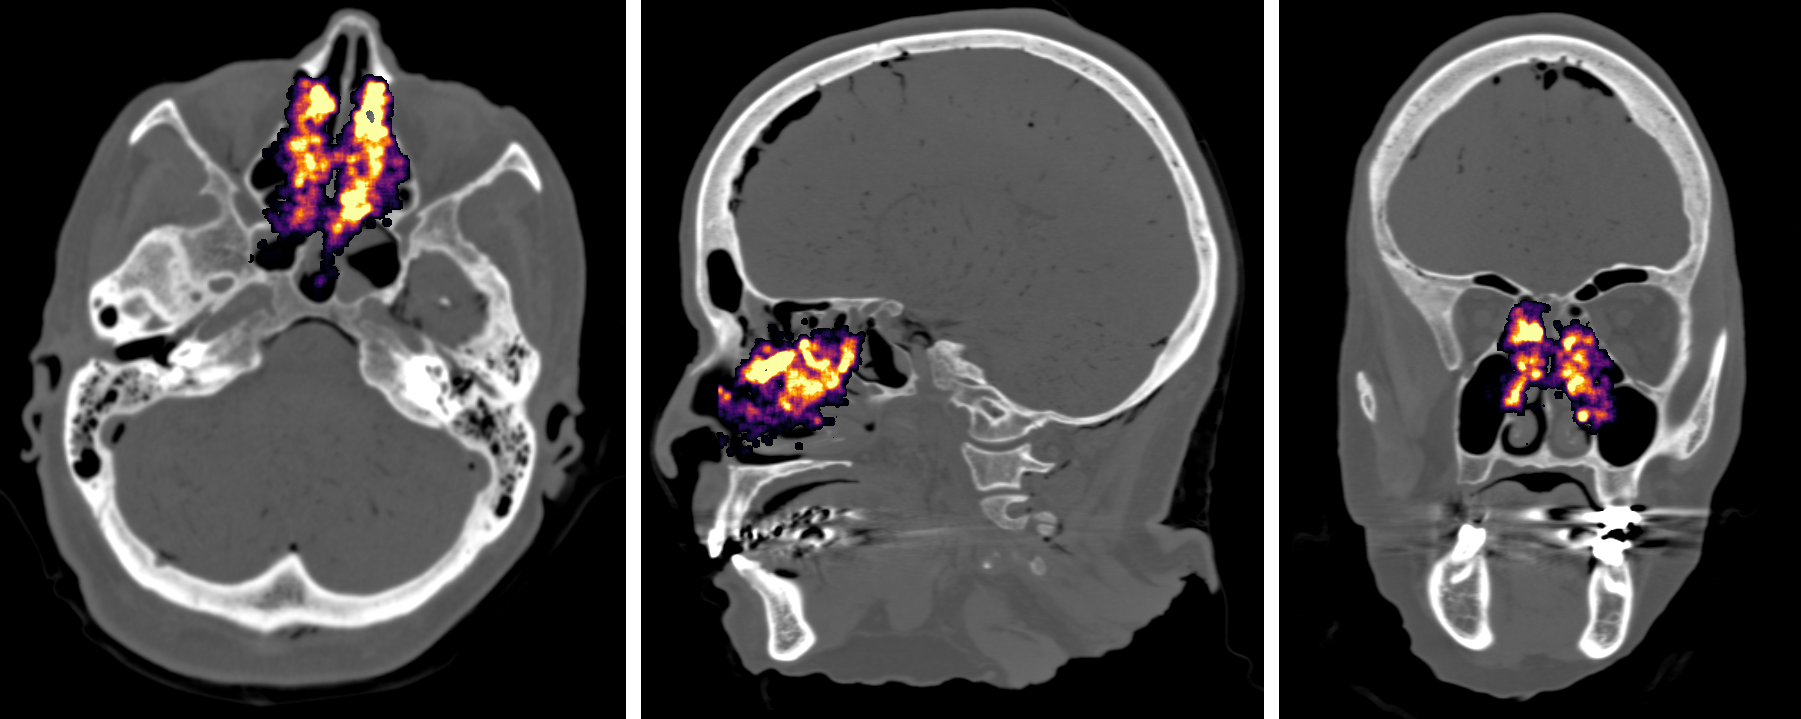

Surgical Completeness Prediction

We use different information to predict surgical completeness and provide real-time feedback to surgeons. Through improving surgical completeness, the revision surgery rate will be dramatically decreased.

Surgical Removal Prediction based on Instrument Motion

Surgical Removal Prediction based on SurgicalSLAM.